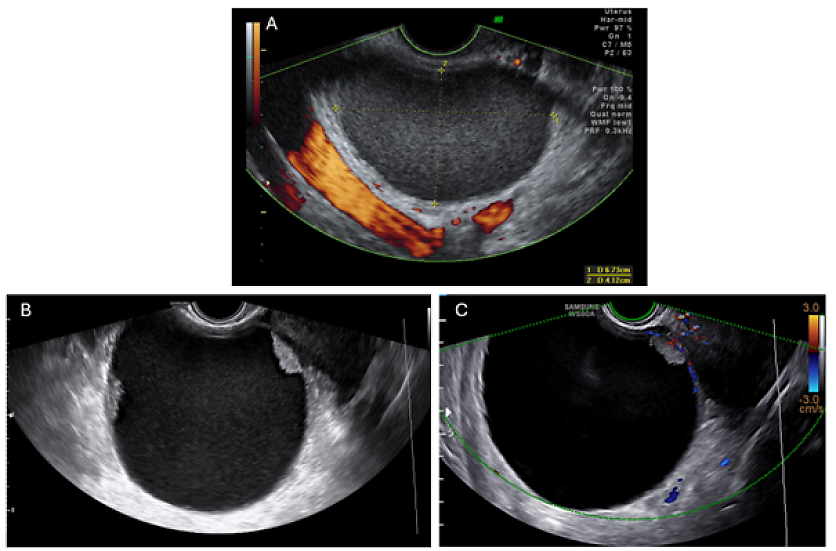

Ovarian cancer (e.g. clear cell cancer or endometrioid adenocarcinoma) may exhibit similar features to those of endometriomas, especially in menopausal women (Figure 29). In addition, malignancies may develop in endometriomas (malignant transformation). The presence of vascularized solid components/papillary projections in a presumed endometrioma is alarming and warrants further investigation.47 Serum CA 125, a tumor marker for ovarian cancer, is often elevated in patients with endometriosis and correlates with the severity of the disease.48 This limits its utility in distinguishing between a benign endometrioma and malignancy in premenopausal women.

29

Ultrasound imaging of a histologically confirmed clear cell carcinoma arising from an endometrioma. In Image A, a unilocular lesion with ground-glass echogenicity and smooth wall is visible. After 3 years of follow-up, significant change was noted, including an increase in size of the maximum diameter of the lesion from 67 mm to 117 mm and a morphological transformation from a unilocular cyst to a unilocular-solid lesion with four vascularized papillary projections (Images B and C).